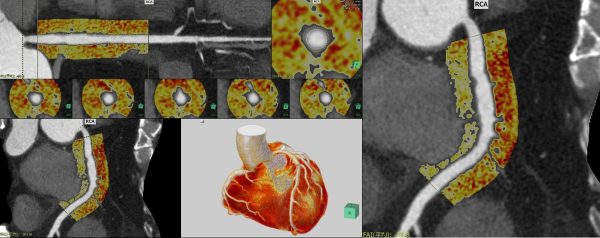

循環器領域の機能アップデート

心臓の動きを補完してより滑らかな4D画像表現を行うことができる「心臓4Dビューア」を新たにラインアップする。非剛体位置合わせの補完技術により、拍動する心臓の4DCT画像から滑らかな4D画像表現が可能である。また、冠動脈解析(CT)内の機能として、血管周囲の炎症の指標として近年関心が高まっている冠動脈脂肪組織濃度(FAI)の計測機能を追加する。循環器領域のご要望に応える機能を搭載し、医療の質向上に貢献する。